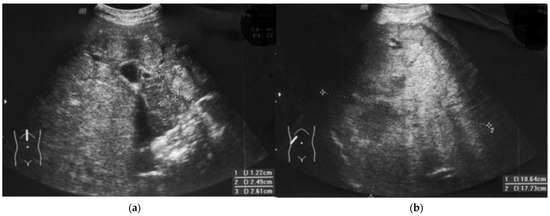

Figure 2.

Fulminant hepatocellular carcinoma HCC progression in a patient with immunodeficiency. Regularly (every 3 months) performed ultrasound examinations (liver, spleen, lymph nodes) did not show any changes in October, but the ultrasound image showed heterogenous nodules (January), (a) that resemble nodular regenerative hyperplasia, typical for CVID [2]. The first blind liver biopsy (January) was non-diagnostic. Afterwards, a 110 mm tumor developed, and HCC was confirmed by second biopsy (April). Finally, fulminant growth up to 180 mm was observed despite lamivudine therapy, vaccination, normal ALT, and high anti-HBs level (b).

The patient had progressive resistant thrombocytopenia (till 30–40 × 103/μL) and coagulopathy (see below). At this stage (February), the patient was not qualified for surgery. Due to B cells < 1%, there was no target for rituximab. IVIG dose was increased for the treatment of thrombocytopenia in CVID [2] (Figure 1). Further on, computer tomography showed 11 cm intrahepatic tumor; afterwards, hepatocellular carcinoma and hepatic cirrhosis were confirmed by core needle biopsy. The first biopsy (January) was non-diagnostic and showed no significant abnormalities, whereas the second (April) (in stage IIIA-IVB HCC) was representative.

2.3. Clinical Course of HCC and Outcome

Weight loss and significant deterioration (Eastern Cooperative Oncology Group (ECOG) status 4) were observed. Due to the patient’s condition, which included the risk of severe complications and immunodeficiency, the patient was disqualified from oncological therapy (e.g., immunotherapy with atezolizumab) by the Tumor Board [15]. Finally, metastases and hepatic encephalopathy were observed with fatal outcome within one month after HCC confirmation, and fast tumor progression was observed in ultrasonography (Figure 2b).